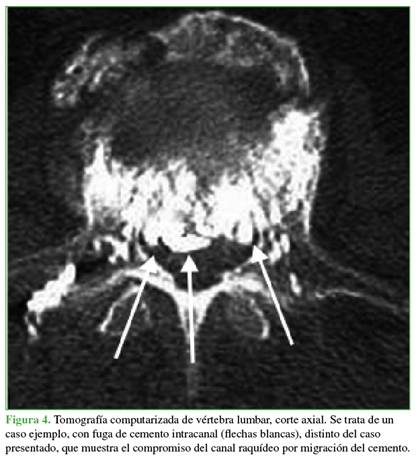

Mecanismos en la cifoplastia: pueden ser directos o indirectos. Como mecanismo directo se puede mencionar la migración intracanal del cemento (Figura 4) que, por efecto de masa o térmico, puede lesionar estructuras nobles. Se ha descrito también el aumento crítico de la presión intravertebral, más frecuente en la técnica bipedicular.4 Los mecanismos indirectos son el embolismo arterial por micropartículas de cemento que ocluyen la arteria espinal anterior o la arteria de Adamkiewicz, la congestión del plexo venoso de Batson y el efecto térmico de la polimerización del cemento.5 En nuestro paciente, según las imágenes del control posoperatorio, se descartó la fuga del cemento en el canal (Figura 4).